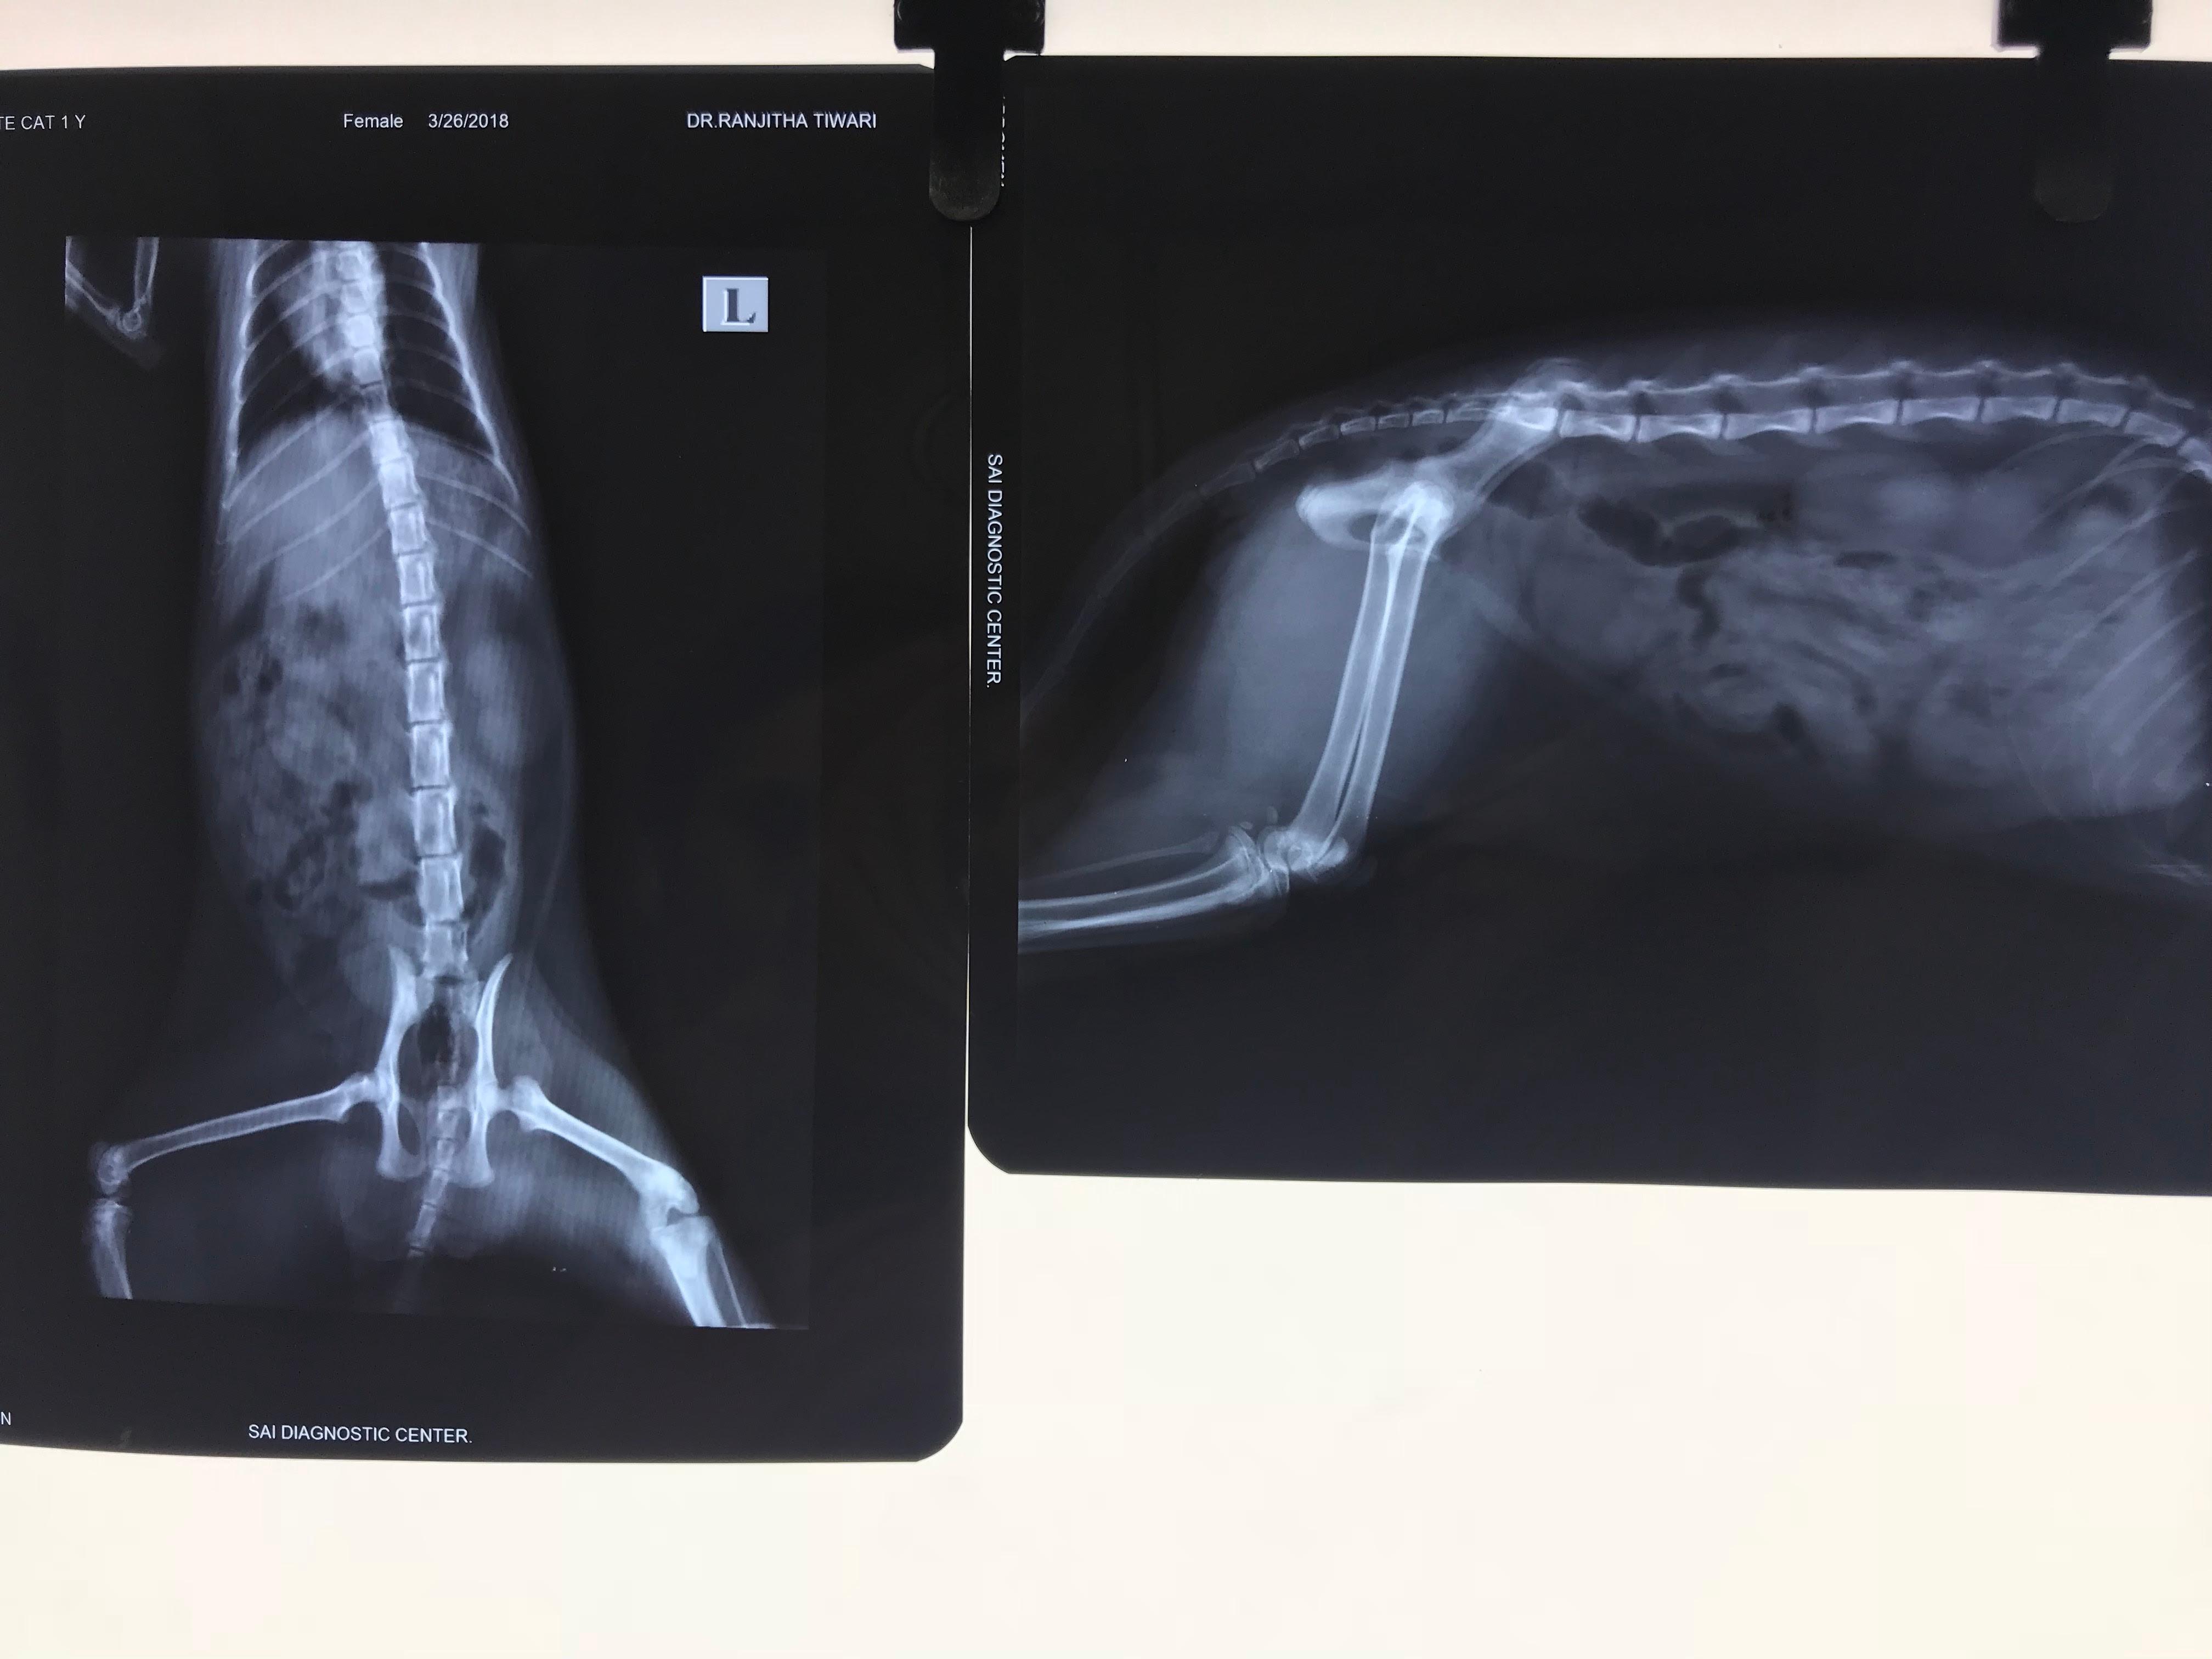

my cat has not returned to heat since 5 weeks from her last heat cycle which was her first heat cycle.the vet told me to take a x ray for her as she felt her uterus was bulged. but the x ray showed no such signs of bulging instead gas packets were formed.so is this causing her from not coming to heat? i will attach the x ray does it show any signs of pyometra

Hello. I do not see any evidence of pyometra or enlargement of the uterus. If this were to happen, Snowwhite would also be showing signs of illness, such as lethargy, loss of appetite, increased thirst & vomiting. Gas in the intestines is not always a sign of any particular disease as it can occur with some dietary sensitivities. I would give her more time to see if she comes into heat. If she does not it might be a good idea to consider spaying her as other abnormalities such as cystic ovaries may be at fault. But for now, just give her a few more weeks to see if she cycles again. Thanks for using Petco Pet Education Center, formerly Petcoach.